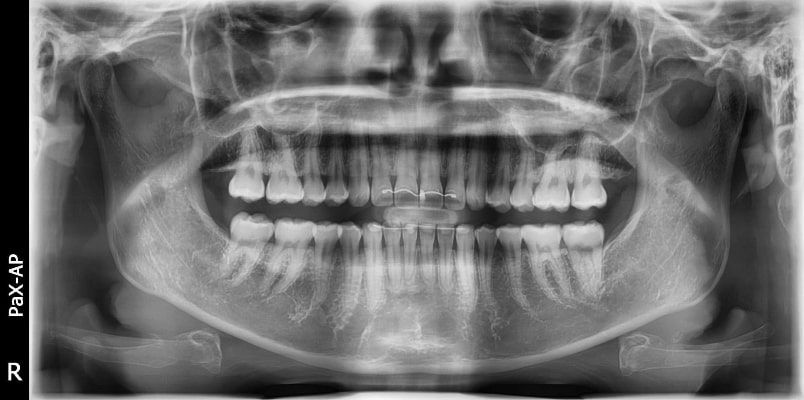

El innovador FOV proporciona un volumen en forma de arco que muestra una vista más amplia de la dentición en comparación con otros dispositivos del mismo FOV.

Normalmente, una imagen de 10x8.5 muestra el diente No.8. Sin embargo, cuando los terceros molares están tumbados sobre su lado hay una gran posibilidad de que el diente se corte de la imagen.

El “volumen en forma de arco” elimina esta posibilidad y muestra el área de dentición oculto.